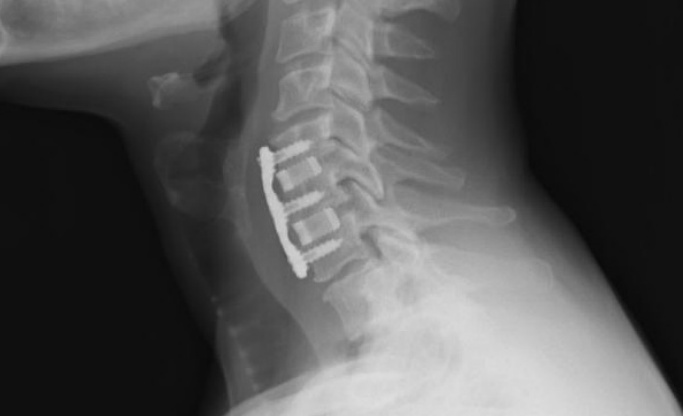

頸椎、脊柱

由氮化硅復合材料制作的頸椎間隔器和脊柱融合器已投入使用,并取得了成功的臨床結果。尤其在脊柱方面,多孔氮化硅制備的脊柱椎間體融合手術的植入材料,在澳大利亞的臨床應用已經超過15年;致密氮化硅在美國的脊柱應用中植入超過3年。

氮化硅頸椎植入物(圖片來源:Sintx)